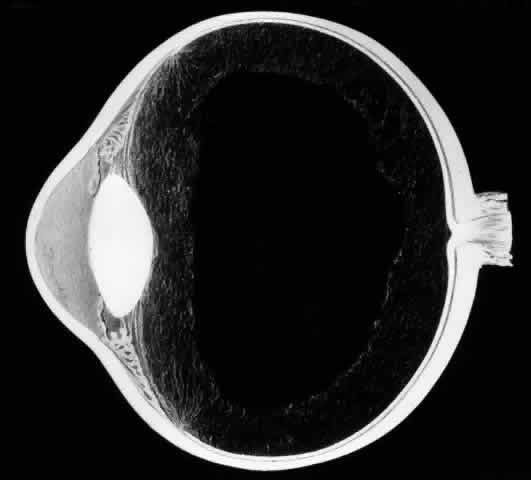

Biomicroscopic Findings Preceding Development of a Giant Tear

The earliest biomicroscopic changes preceding the development of a giant retinal tear were syneresis and liquefaction of the vitreous gel, converting the posterior and central portions of the vitreous body into a large lacuna (Fig. 14). Later, the anterior gel became condensed, and its posterior aspect formed an equatorially oriented membrane extending across the vitreous cavity (Fig. 15). This membrane did not oscillate with ocular movements, suggesting that it was under tension. Marked contraction of this membrane seems responsible for tearing the retina along the posterior border of the vitreous base (Fig. 16). Liquefied vitreous gel facilitated inversion of the posterior retinal flap (Fig. 17).

Fig. 15. In later biomicroscopic changes preceding a nontraumatic giant retinal break, the anterior vitreous gel becomes condensed and a membrane forms its posterior aspect.

Fig. 16. Contraction of this equatorially oriented membrane extending across the vitreous cavity produces a giant tear along the posterior border of the vitreous base.